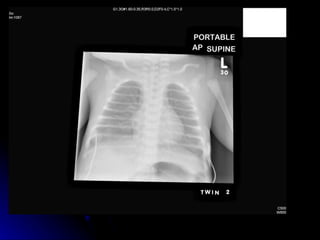

Pneumothorax Clinical:- Maybe asymptomatic May be life threatening Sudden deterioration in gas exchange Poor colour Hypotension and tachycardia Unilateral overexpanded thorax

• 25.

• 26.

Pneumothorax - aetiologyUneven alveolar ventilation Air trapping and high pressure swings Tracking of air from pulmonary interstitial emphysema